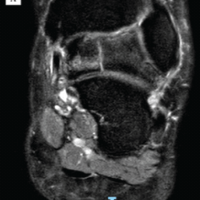

Under regional anesthesia and tourniquet control, a longitudinal incision was made over the swelling. Intraoperatively, a large fascial defect measuring approximately 9 × 3 cm was identified with herniation of the tibialis anterior muscle (Fig. 2).

Figure 2: Intraoperative photograph.